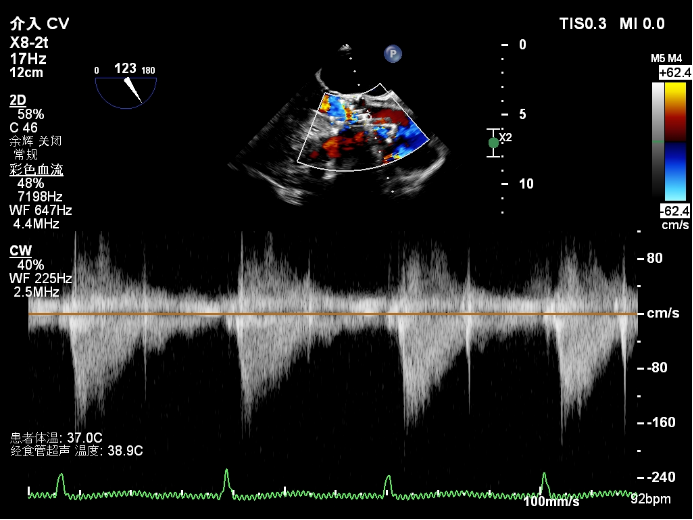

3. 心脏超声/经胸超声心动图

下腔静脉(inferior vena cavaIVC)直径及其呼吸变异度是评估右心房压力和容量状态的重要无创指标。这对判断心功能(尤其是右心)、循环容量及液体反应性有重要临床意义。

图片

3.1  为什么要评估IVC

1)反映右心房压力:IVC直接汇入右心房,其直径和塌陷程度受右房压力影响。

2)评估容量状态:IVC扩张且固定:提示容量超负荷或右心衰竭(如心衰、肺高压)IVC塌陷明显:提示容量不足(如脱水、出血)

3预测液体反应性:在机械通气患者中,IVC呼吸变异度可预测补液后心输出量是否增加。

3.2  临床应用场景

1)心力衰竭评估:IVC扩张+低塌陷度→提示右心衰或容量超负荷,需利尿治疗。

2)休克鉴别诊断:低血容量性休克IVC细小+高塌陷心源性休克:IVC扩张+塌陷消失

3)指导液体管理:机械通气患者扩张指数18%→可安全补液

4肺动脉高压随访:IVC持续扩张提示右心功能恶化。